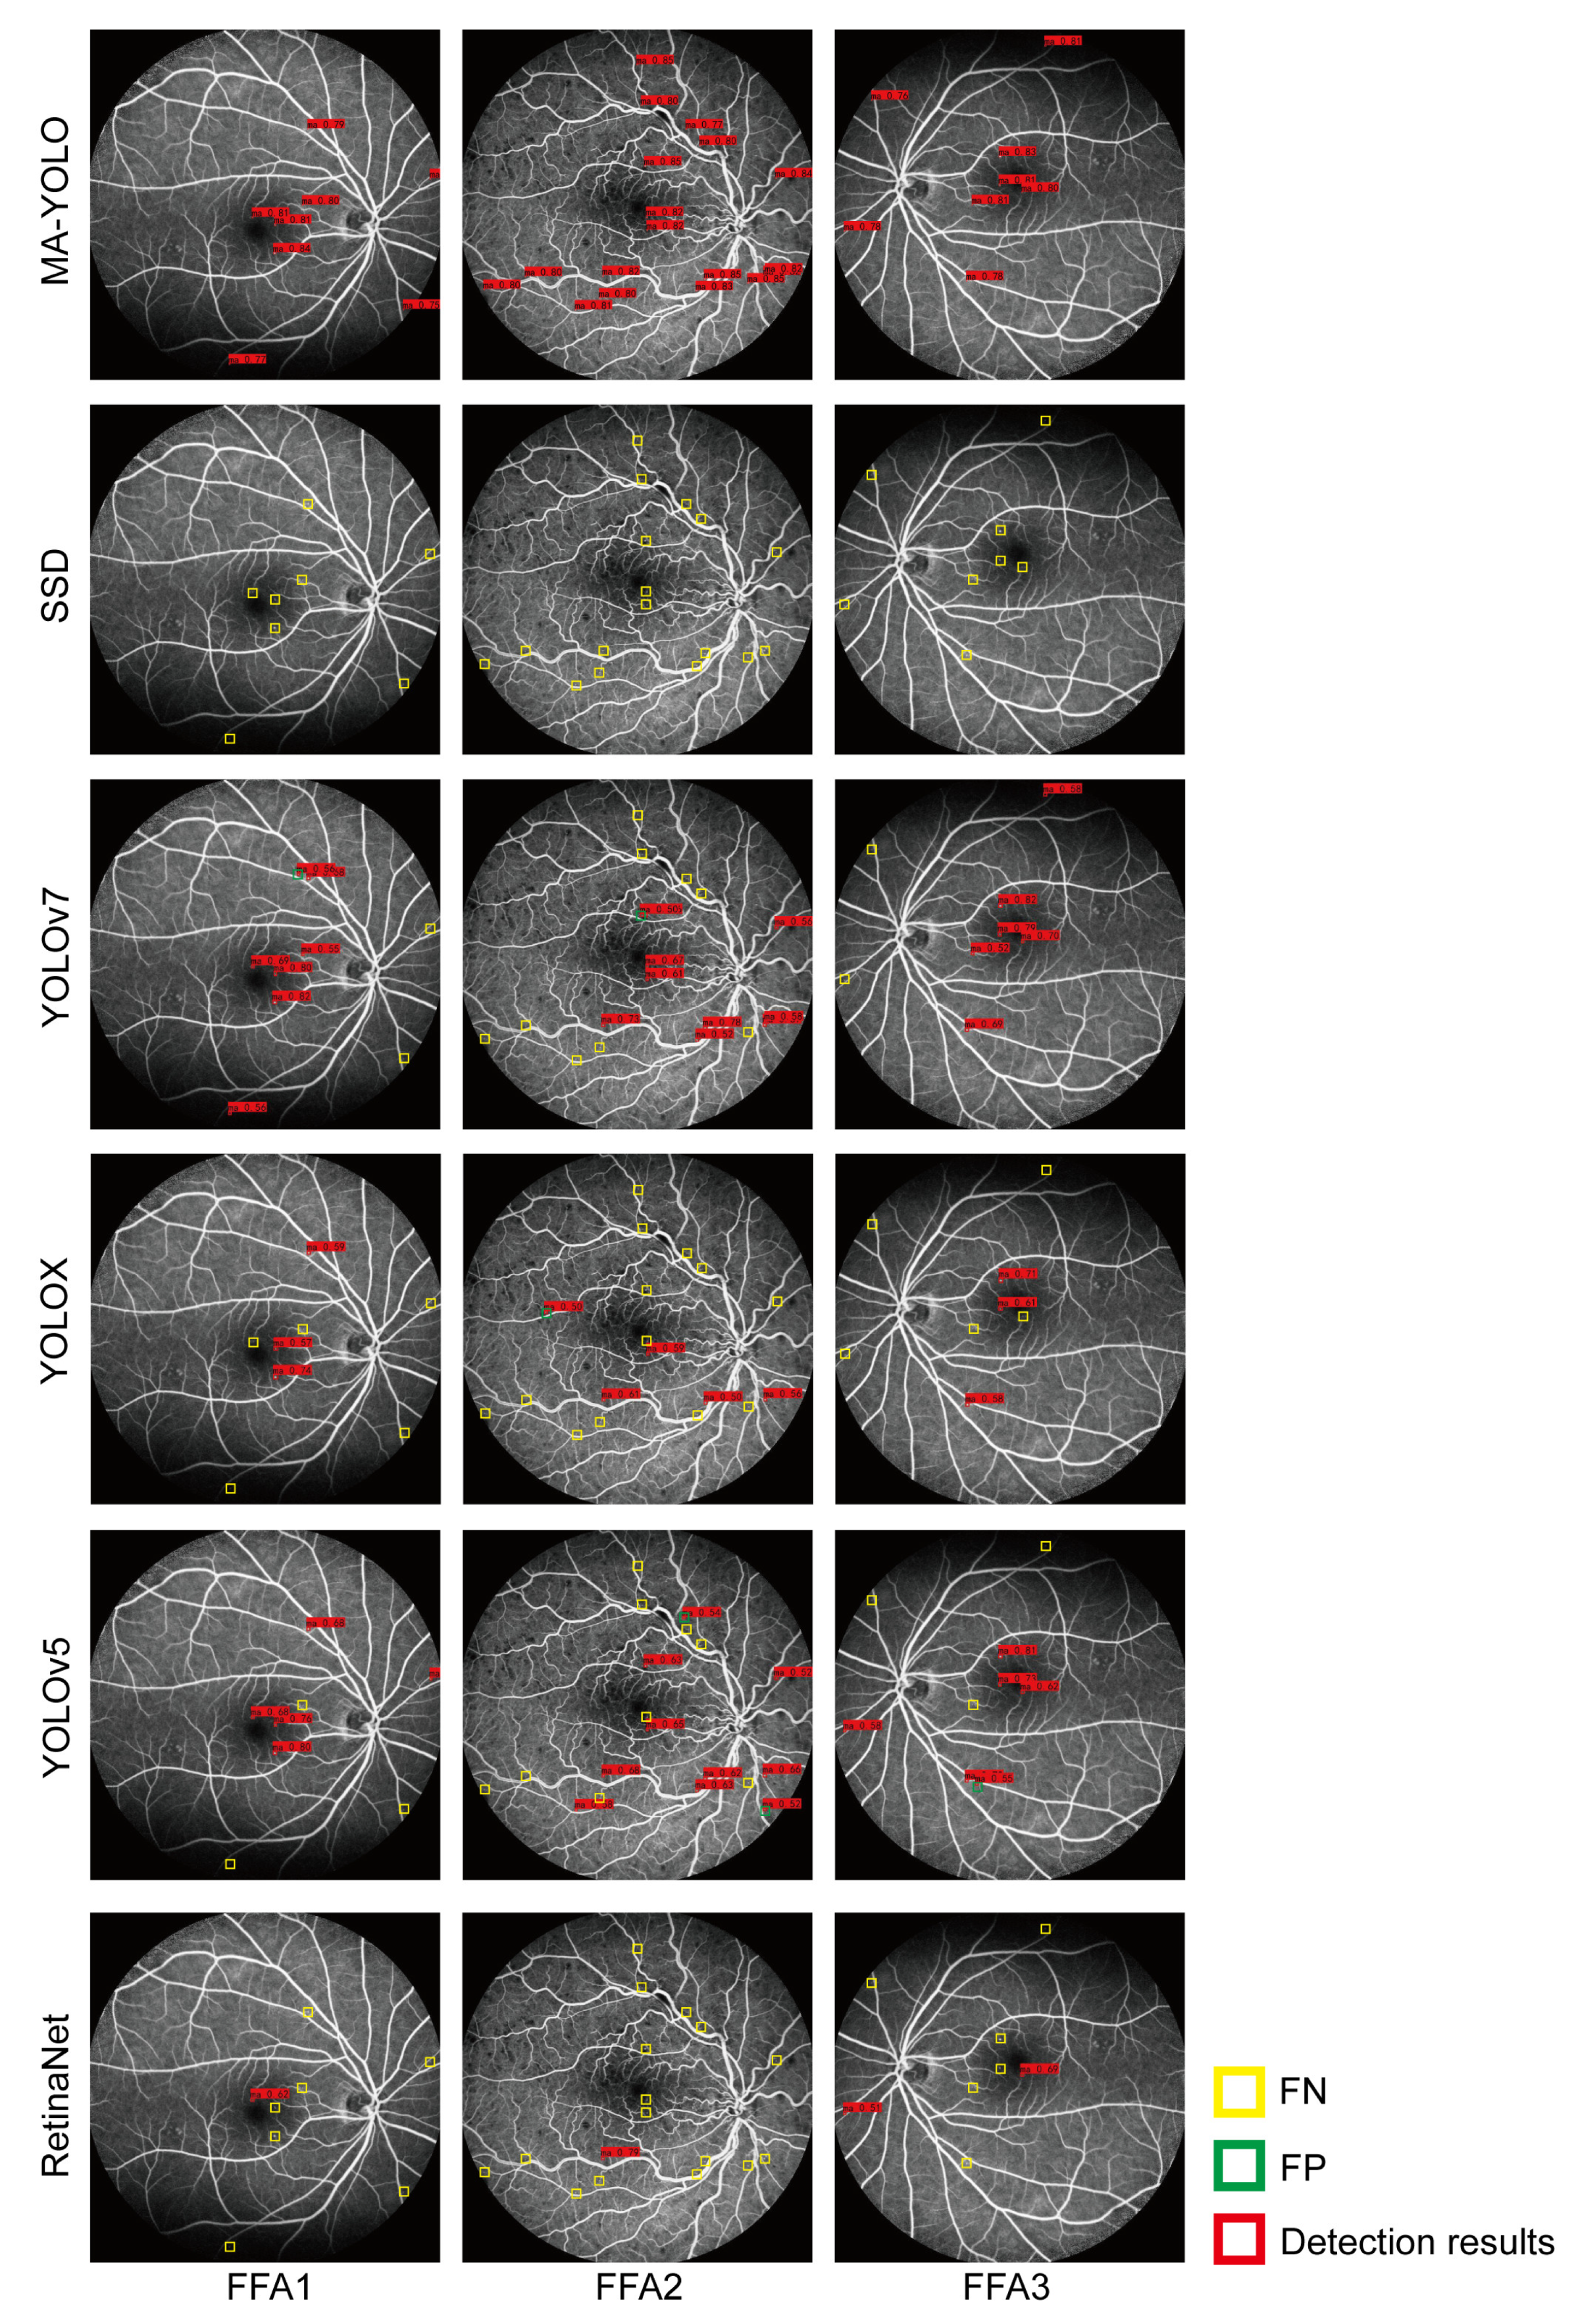

Table 3 and Table 4 show the comparison of MA detection performance and tuning parameters during the training phase among different models. Figure 10 shows the MA detection results of different models, where the red boxes represent the detection results with a confidence score greater than 0.5, the yellow boxes indicate missed detection, and the green boxes represent false positive detection. Table 5 shows the comparison of the MA detection performance of different object recognition models reported in various studies.

According to Figure 10 and Table 3 and Table 4, the detection results of MA-YOLO were close to ground truth. Part of the background was mistakenly detected by the YOLOv5, YOLOX, and YOLOv7 models. We observed some missed MA detections by the SSD, RetinaNet, YOLOv5, YOLOX, and YOLOv7 models. MA-YOLO achieved the highest Re, Pre, F1, and AP scores compared to the other models and a higher FPS score than RetinaNet. According to Table 5, the detection performance of MA-YOLO was superior to that of the other examined methods.

Figure 10. MA detection results by different models.